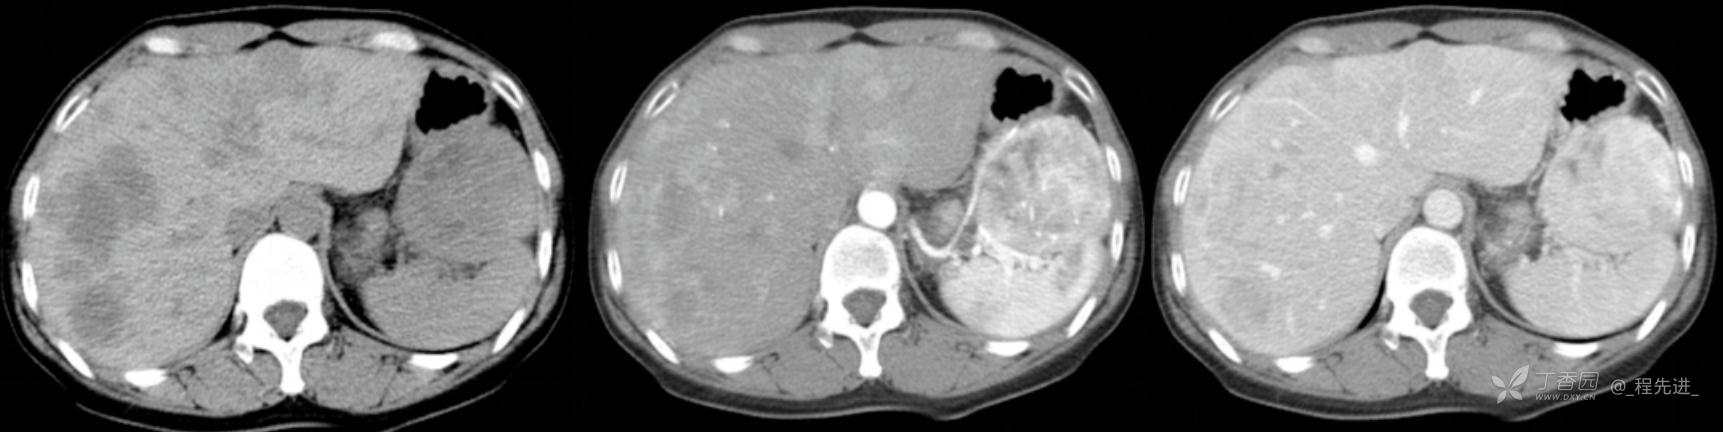

图像左边为平扫,中间的是动脉期,右边的是静脉期